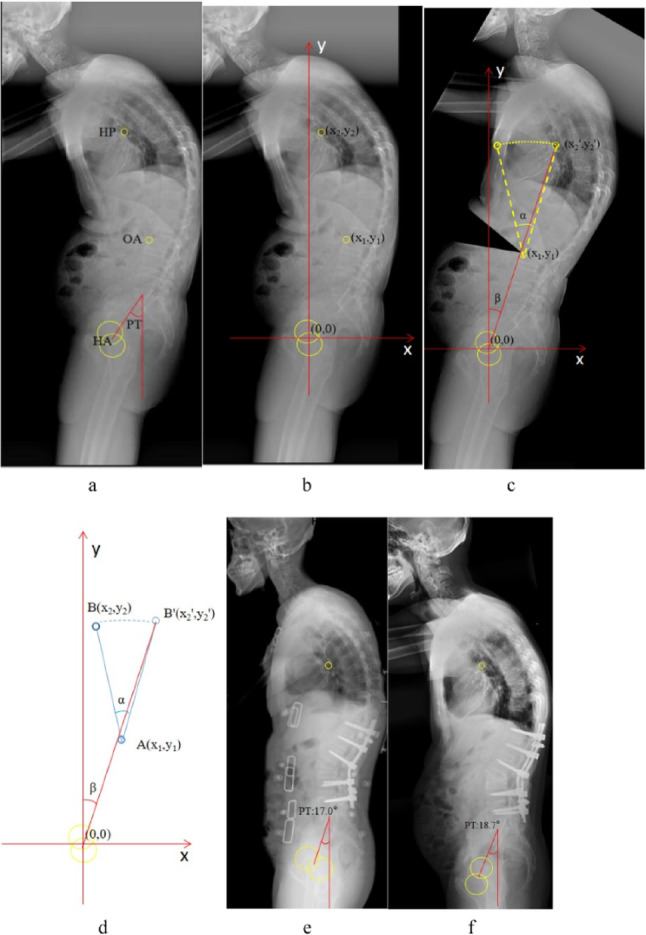

Methods: A total of 20 patients with AS, including 19 men and one woman, who underwent three-column osteotomy from April 2017 to April 2021, in the study hospital were retrospectively reviewed. Spinopelvic parameters, including global kyphosis, pelvic incidence, sacral slope, PT, sagittal vertical axis, horizontal distance between hip axis and hilus pulmonis (HDHH), measured on preoperative, postoperative, and final follow-up radiographs were analyzed. A coordinate diagram was created on the lateral spine radiographs with the hip axis as the origin. The distances and angles between the osteotomy apex, hilus pulmonis, and hip axis were measured, and a mathematical model was established using basic vector functions. The planned osteotomy angle was substituted into the mathematical model to obtain precalculated postoperative PT. Paired sample t-test was performed to determine the differences between planned osteotomy angle and actual osteotomy angle and between predictive postoperative PT and actual postoperative PT.

Results: Seven patients underwent single-level osteotomy, and 13 patients underwent two-level osteotomy. No significant difference was observed between the planned osteotomy angle and the actual osteotomy angle. No statistically significant difference was found between the precalculated postoperative PT and the actual postoperative PT.

Conclusions: The novel mathematical model was reliable in predicting postoperative PT in patients with AS undergoing three-column osteotomy.